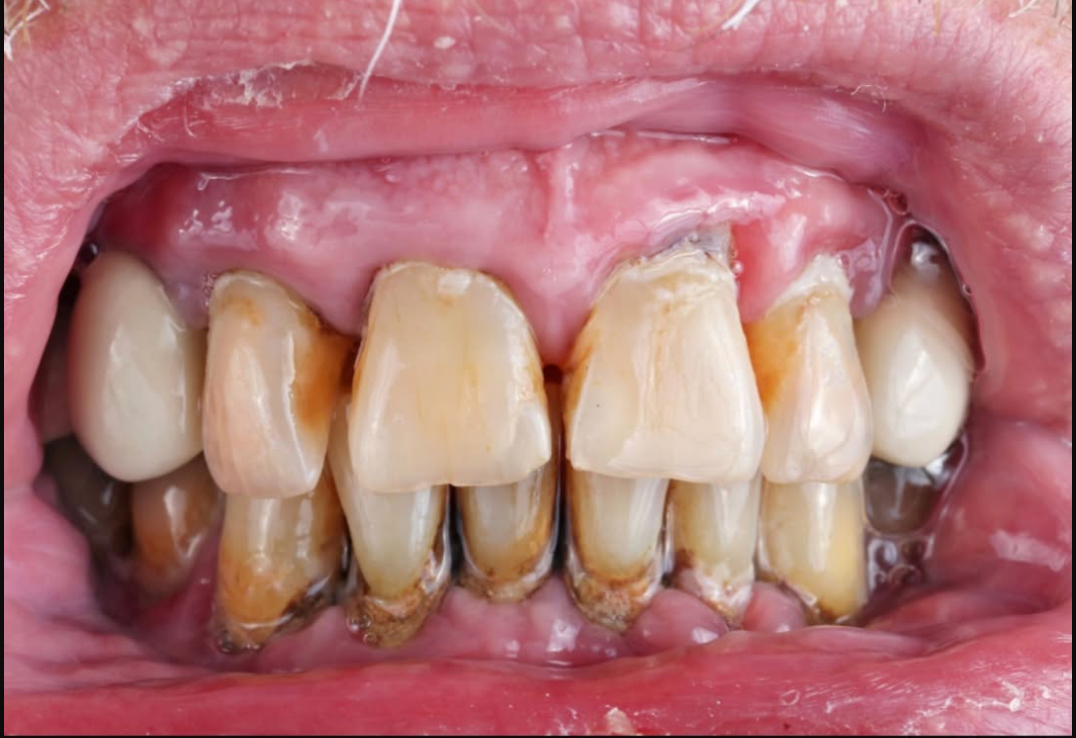

Sipas studimit, personat me më shumë dhëmbë të humbur apo të dëmtuar rezultojnë të kenë një rrezik më të lartë për të vdekur më herët, ndërsa ata me dhëmbë të shëndetshëm ose të trajtuar kanë një probabilitet më të ulët.

Studiuesit theksojnë se jo vetëm dhëmbët natyralë, por edhe ata të trajtuar apo të mbushur, konsiderohen faktor pozitiv në parashikimin e jetëgjatësisë.

Një nga arsyet kryesore lidhet me faktin se problemet dentare mund të shkaktojnë inflamacion kronik, i cili lidhet me sëmundje serioze si ato kardiovaskulare apo diabeti.

Gjithashtu, mungesa e dhëmbëve ndikon në ushqyerje, pasi individët kanë më shumë vështirësi në përtypje dhe shpesh orientohen drejt ushqimeve më të buta, por më pak ushqyese.